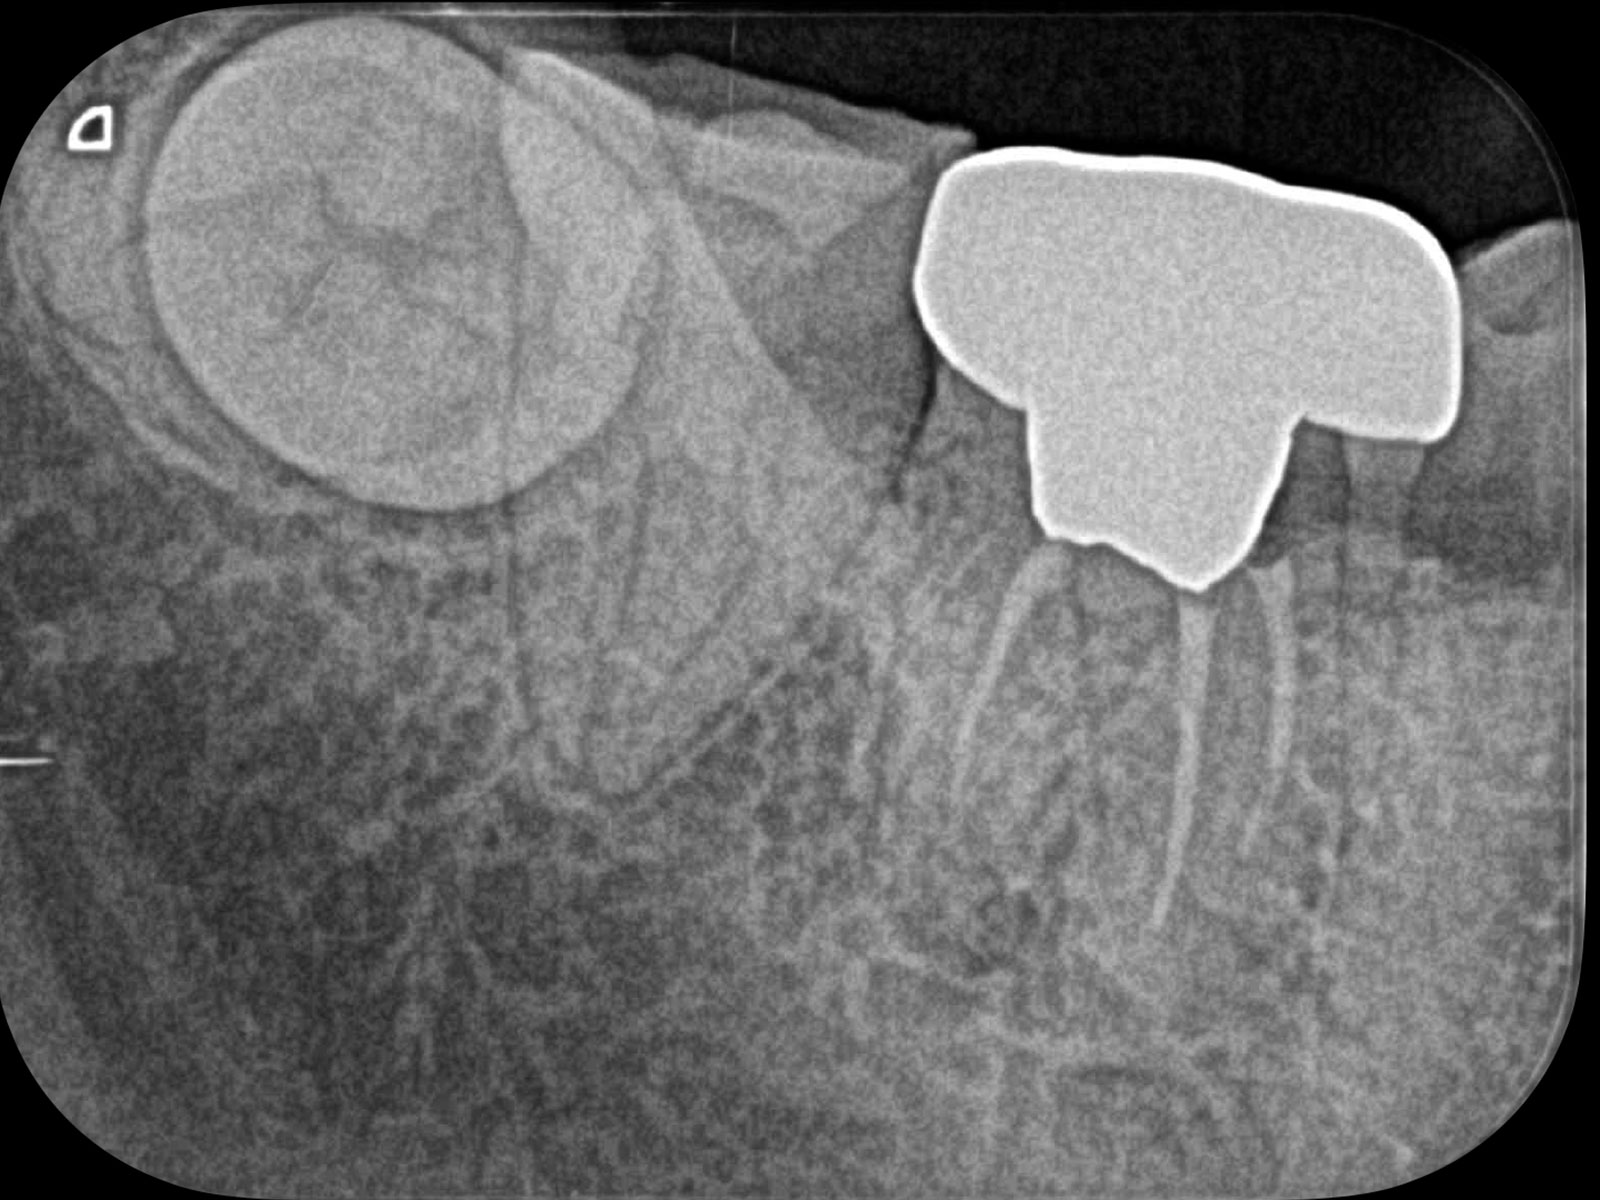

「CT」は画像診断装置の一種です。3次元的(立体的)に治療部位を撮影できるため、血管や神経の位置関係など、通常のレントゲンでは得られない情報も得ることができます。

上記の画像は、CT(左)とレントゲン(右)の比較です。丸をつけている箇所が病巣なのですが、レントゲンだと発見できないことがおわかりいただけるかと思います。